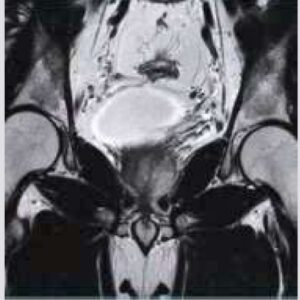

Body Imaging

The Body Suite is specialized for Clinical body examinations.